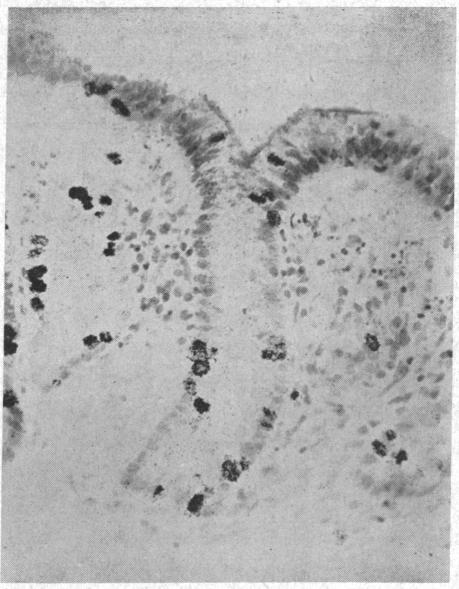

IN VITRO STUDY OF HUMAN RECTAL EPITHELIAL CELLS. I. ATYPICAL ZONE OF H3 THYMIDINE INCORPORATION IN MUCOSA OF MULTIPLE POLYPOSIS.

J Clin Invest. 1963 Dec;42(12):1922-8. doi: 10.1172/JCI104878.

IN VITRO STUDY OF HUMAN RECTAL EPITHELIAL CELLS. I. ATYPICAL ZONE OF H3 THYMIDINE INCORPORATION IN MUCOSA OF MULTIPLE POLYPOSIS.人直肠上皮细胞的体外研究。I. 多发性息肉病黏膜中H3胸腺嘧啶核苷掺入的非典型区域。